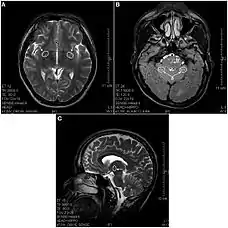

(A) T2-изображение отдела мозга, показывающее дегенеративные гиперинтенсивные пятна в базальном переднем мозге (показано стрелками). (B) T2-изображение, показывающее гиперинтенсивную дегенерацию в мозжечке (a) и в варолиевом мосту (b). (C) Сагиттальное T2-изображение, показывающее дегенеративные пятна в промежуточном мозге (таламус).

В 2013 году вышла статья в которой впервые были использованы МРТ снимки при описании повреждений мозга у принимавших кетамин людей[3]. В выборке участвовали 21 человек со стажем употребления кетамина от 0,5 до 12 лет в дозах от 0,2 до 3 грамм ежедневно. Обнаружены многочисленные лезии во многих областях мозга появляющиеся после 2—4 лет употребления диссоциатива, а также, атрофия коры во фронтальной, теменной и затылочной областях. Есть указания на то, что в результате воздействия кетамина многие структуры человеческого мозга могут получить хронические повреждения, отличные от повреждений от других психоактивных веществ воздействующих на ЦНС (например, кокаина, героина, метамфетамина)[3].